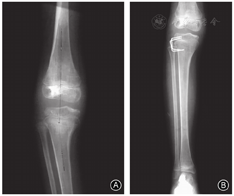

女,6岁,因右膝严重外翻畸形入院。4年前下楼扭伤膝关节,其后逐渐出现外翻畸形并跛行。体格检查:右膝关节外翻约28°,伸-30°、屈130°,挛缩的髂胫束制约膝关节伸直,髌骨固着在外侧,小腿相对大腿于外旋位(图1)。Kujala髌股关节功能评分49分。影像学检查:右膝关节X线片示胫骨后外旋转移位,内侧胫骨平台凸起,髌骨向外侧脱位,股胫角155°,股骨髓内可见致密的条状纹理(图2)。

一期切断髂胫束中挛缩的条索,行胫骨干骨牵引。6周后二期手术,去除骨牵引,行髂胫束和股二头肌肌腱"Z"形延长;在肌间隔剥离股外侧肌,骨膜下推开股四头肌,髌骨处切断股外侧肌腱膜并上移固定在股四头肌腱外侧,切开髌外侧支持带,松解髌骨,完成外侧软组织松解。在髌骨内缘切断股内侧肌腱膜,外移固定在股四头肌腱前侧;重叠缝合髌内侧支持带;鹅足前移,固定在髌腱内侧,强化内侧软组织稳定。胫骨内侧平台隆凸阻碍胫骨完全复位(图3),因此在胫骨内侧平台前缘切开小口,刮除少量骨质,按压平台隆凸,使之与股骨内髁匹配。术中未发现异位钙化组织。术后用斯氏针经髁间交叉固定膝关节于屈曲20°位,长腿石膏托固定。5周后拔除斯氏针并开始进行膝关节屈伸活动锻炼,6周后扶双拐轻负重行走。

术后4个月,因胫骨内翻畸形行近端骨骺外侧阻滞术,6个月后获得矫正(图4)。术后10个月,因下肢内旋和股骨超长2 cm,行股骨下端外旋短缩截骨术,3个月后截骨愈合。